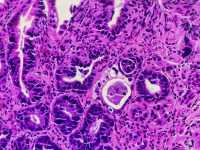

男66岁胃窦剥脱样糜烂

慢性萎缩性胃炎伴肠化、糜烂。可见修复性改变。